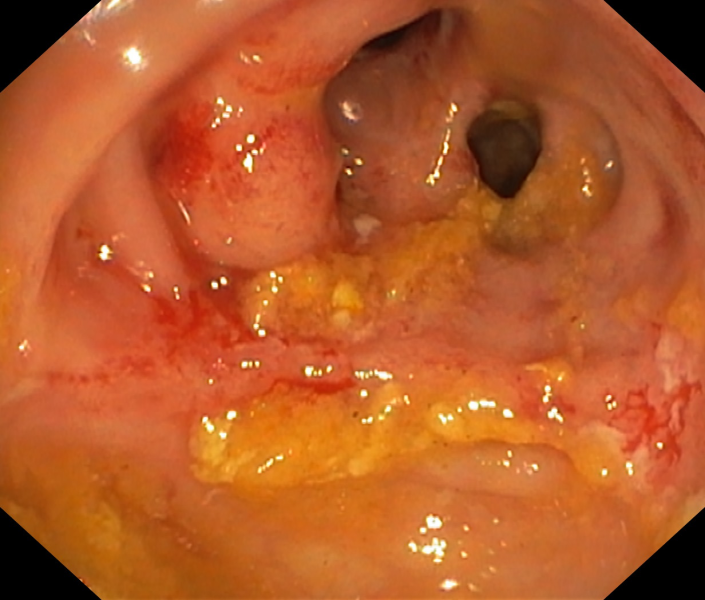

Fistulizing Crohn’s Disease in a pediatric patient

Fotografia